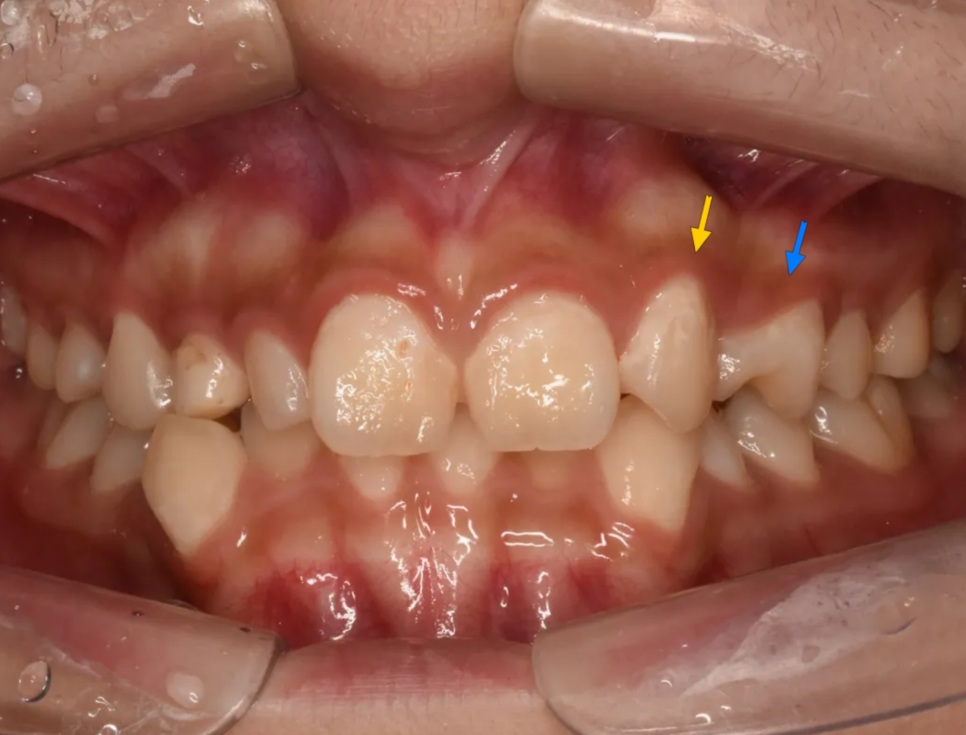

다음으로 눈에 띄는 것은 있어야 할 이가 없는 경우(결손치)인 경우입니다. 아래 그림에서 표시된 이는 작은앞니(측절치)위치에 있지만 실제로는 송곳니입니다. 즉 작은앞니가 없는 공간으로 뒤쪽에 있던 송곳니가 밀려나온 경우입니다. 그리고 공간이 남기 때문에 그 뒤의 작은어금니가 공간을 채우면서 회전되어 있는 것이 보입니다.

노랑: 결손된 측절치 위치로 밀려나온 송곳니 / 파랑: 공간을 채우느라 회전한 작은어금니